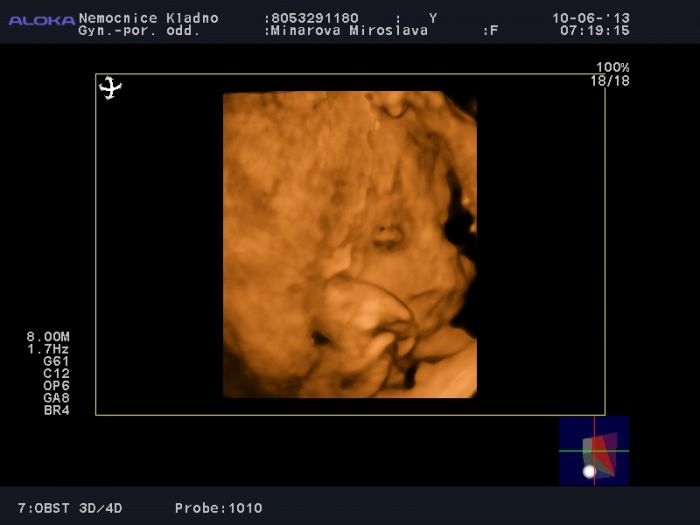

Na tadyté mi taky připomíná víc kluka. A co tady? Není tam tolik přez placentu vidět hlavička, ale obliče vcelku ano..

Na tu fotku kašli, kdo to čte, tak ví, že je tvoje. Takhle to už totiž sama nezměníš... Jo a taky to vidím spíš jako kluka